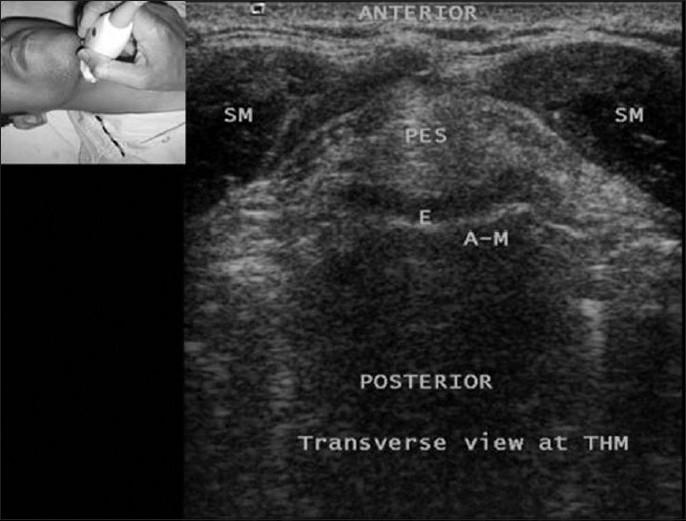

Currently, the role of ultrasound (US) in anaesthesia-related airway assessment and procedural interventions is encouraging, though it is still ill defined. US can visualise anatomical structures in the supraglottic, glottic and subglottic regions. The floor of the mouth can be visualised by both transcutaneous view of the neck and also by transoral or sublinguial views. However, imaging the epiglottis can be challenging as it is suspended in air. US may detect signs suggestive of difficult intubation, but the data are limited. Other possible applications in airway management include confirmation of correct endotracheal tube placement, prediction of post-extubation stridor, evaluation of soft tissue masses in the neck prior to intubation, assessment of subglottic diameter for determination of paediatric endotracheal tube size and percutaneous dilatational tracheostomy. With development of better probes, high-resolution imaging, real-time picture and clinical experience, US has become the potential first-line noninvasive airway assessment tool in anaesthesia and intensive care practice.

目前,超声(US)在麻醉相关气道评估和操作干预中的作用令人鼓舞,尽管其作用仍未明确界定。超声可以可视化声门上、声门和声门下区域的解剖结构。通过颈部的经皮视图以及经口或舌下视图都可以看到口腔底部。然而,会厌悬浮于空气中,对其成像可能具有挑战性。超声可能检测到提示困难插管的迹象,但相关数据有限。气道管理中的其他可能应用包括确认气管内导管的正确位置、预测拔管后喘鸣、插管前评估颈部软组织肿块、评估声门下直径以确定小儿气管内导管尺寸以及经皮扩张气管切开术。随着更好的探头的发展、高分辨率成像、实时图像和临床经验的积累,超声已成为麻醉和重症监护实践中潜在的一线无创气道评估工具。